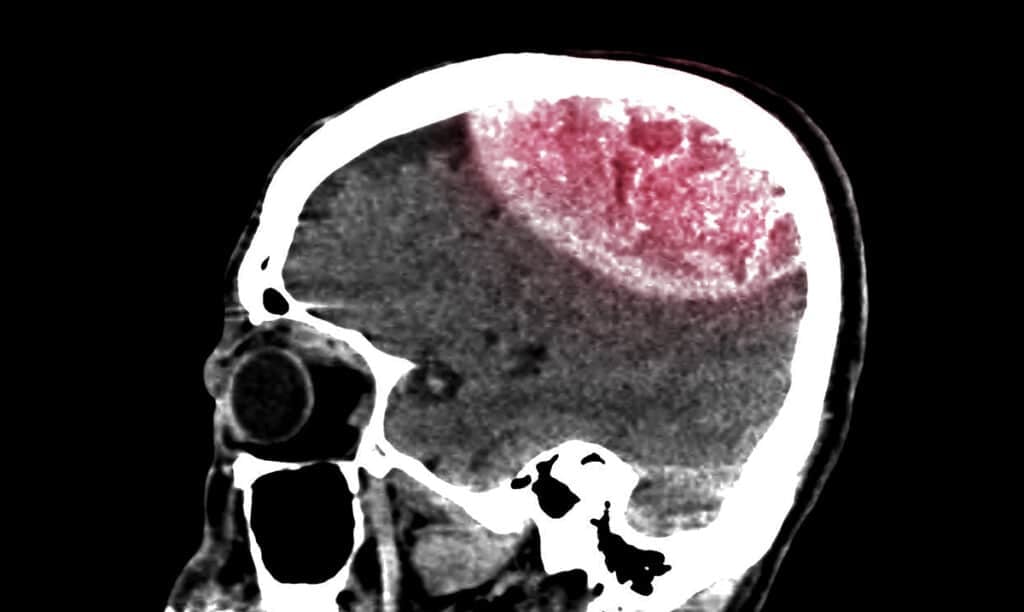

After You Die, Your Brain Knows You’re Dead, Terrifying Study Reveals

nypost.comAfter you die, your brain knows you’re dead, terrifying study reveals

nypost.comAfter you die, your brain knows you’re dead, terrifying study reveals

Researchers Believe That After Death, You Know You’ve Died - GOOD

www.good.isResearchers believe that after death, you know you’ve died - GOOD

www.good.isResearchers believe that after death, you know you’ve died - GOOD

When You Die You Actually Know You’re Dead And Here Is Why

en.protothema.grWhen you die you actually know you’re dead and here is why …

en.protothema.grWhen you die you actually know you’re dead and here is why …

When You Die You Know You Are Dead, According To Scientists – Awareness Act

awarenessact.comWhen You Die You Know You Are Dead, According to Scientists – Awareness Act

awarenessact.comWhen You Die You Know You Are Dead, According to Scientists – Awareness Act